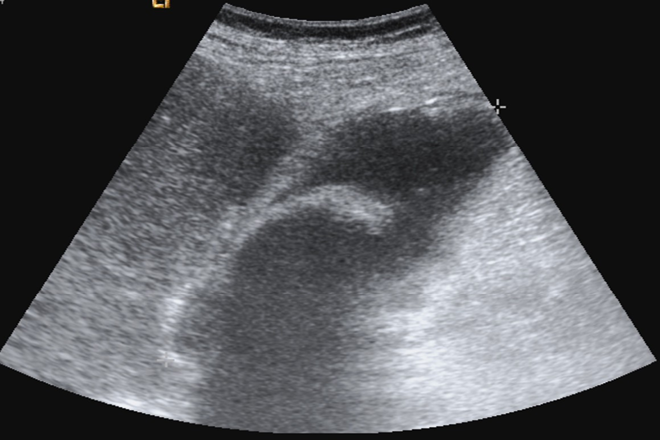

Se evalúa fácilmente con ecografía  sagital y transversal habituales, o con ecografías oblicuas subcostales realizadas con el borde izquierdo del transductor mas cefálico que el borde derecho, la parte frontal del transductor se dirige hacia el hombro derecho, un barrido de cefálico a caudal mostrara la vena hepática media a nivel superior y la fosa de la vesícula biliar a nivel inferior. La fosa discurre desde la superficie anterior de la vena porta derecha en sentido oblicuo hasta la superficie del hígado.

Para la exploración de la vesícula utilizaremos una sonda convex de baja frecuencia (2,5–‐5MHz).No hay normas claramente establecidas  para localizar la vesícula ya que como hemos comentado anteriormente su ubicación es variable y su tamaño también puede modificarse la maniobra mas empleada para localizarla es la denominada“X–‐7”, donde la X indica el inicio de la posición del transductor (bajo el apéndice Xifoides) con el marcador a la derecha del paciente y dirigiendo el haz de ultrasonidos hacia el hombro derecho del paciente El 7 indica que desplazaremos la sonda bajo el reborde costal derecho alrededor de unos 7 cm hasta encontrar la vesícula biliar. En ocasiones puede ser muy útil hacer que el paciente inspire profundamente para que la vesícula se desplace caudalmente por debajo de la parrilla costal. En Casos especialmente difíciles no queda mas remedio que visualizar la vesícula a través de la parrilla costal (en Estos casos puede ser útil utilizar una sonda sectorial de baja frecuencia como la empleada para las exploraciones cardiologicas) o colocar al paciente en decúbito lateral izquierdo. Una Vez localizada la vesícula es preciso explorarla en toda su extensión y para ello necesitamos una vista longitudinal verdadera Esto Se consigue rotando la sonda sobre su eje. Generalmente En la visión longitudinal de la vesícula encontraremos el“signo De exclamación” formado por la vesícula biliar y la vena  porta. En relación con ambos encontraremos la rama de la arteria hepática procedente del tronco celiaco y el conducto biliar común o coledoco, otro de nuestros objetivos de evaluación. Muchas veces es difícil diferenciar la arteria hepática del colédoco ubicados ambos por encima de la vena porta.

En estos casos es muy útil la visión con Doppler color, en la que se detectara flujo en los vasos sanguíneos Finalmente, una vez localizada la vesícula es importante hacer múltiples cortes, tanto transversales como longitudinales, para estar seguro de que no pasar por alto pequeñas litiasis.